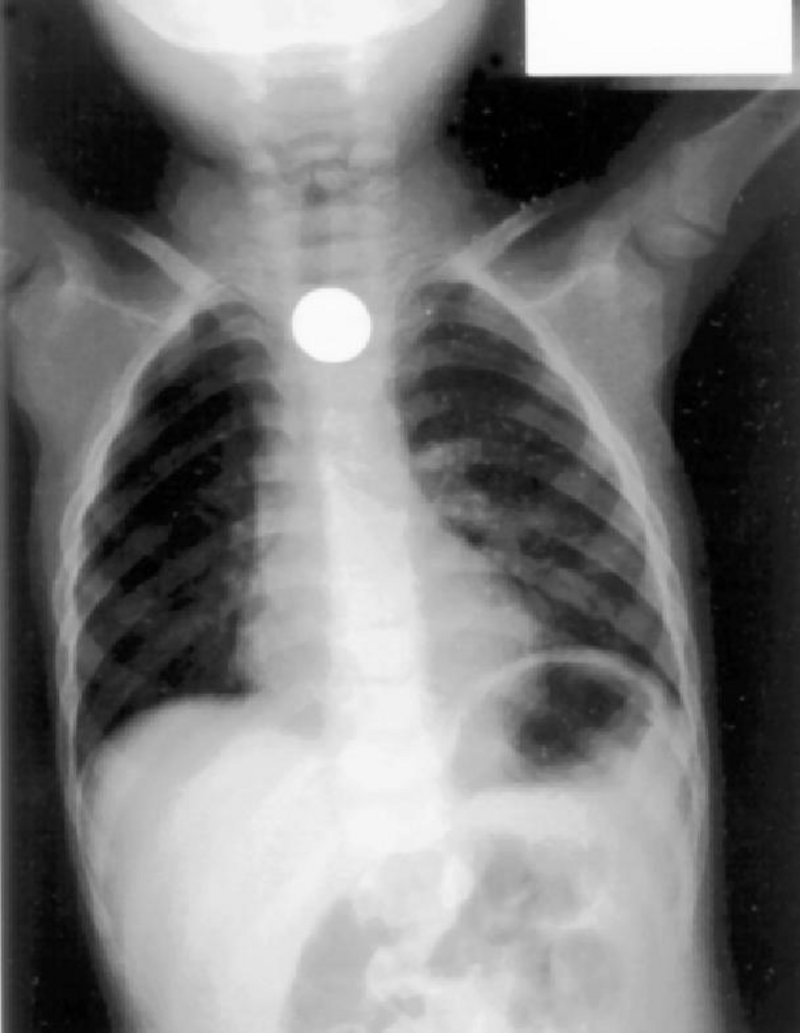

دھاتی چیز نگلنے کا یقین ہونے پر بچے کا پیٹ نہ دبایا جائے (فوٹو: سبق نیوز)

ریاض کے شاہ سعود میڈیکل سٹی کے شعبہ ہنگامی امداد برائے اطفال کے ڈائریکٹر ڈاکٹر فیصل الروقی کا کہنا ہے کہ کوئی ہسپتال ایسا نہ ہو گا جہاں ایسے بچوں کو نہ لایا گیا ہو جنہوں نے کوئی سکہ یا دھاتی چیز نہ نگلی ہو۔ ڈاکٹر فیصل الروقی کا کہنا ہے کہ گذشتہ برس ہسپتال کے شعبہ حادثات برائے اطفال میں ایسے 470 کیسز ریکارڈ کیے گئے جن میں سب سے خطرناک کیس ایک بچے کا تھا جس نے ڈبل اے سائز کا بیٹری سیل نگل لیا تھا۔

’مختلف اشیا نگلنے والے بچوں کی عمر 6 ماہ سے 3 برس کے درمیان تھی۔ ایسے بچے جو مختلف دھاتی چیزیں نگل لیتے ہیں ان کے والدین کو چاہیے کہ وہ فوری طور پر ہنگامی امداد کے شعبے سے رجوع کریں تاکہ بروقت ان بچوں کو طبی امداد مہیا کی جا سکے۔‘

ڈاکٹرالروقی کا مزید کہنا تھا کہ ’ بعض بے پروا والدین کم سن بچوں کے پاس ایسی چیزیں چھوڑ دیتے ہیں جو ان کے لیے خطرناک ثابت ہوتی ہیں۔ والدین کو چاہیے کہ وہ بچوں کا خاص خیال رکھیں، اگرانہیں اس امرکا یقین ہو جائے کہ بچے نے کوئی معدنی چیز نگل لی ہے تو بچے کے پیٹ کو قطعی طور پر نہ دبائیں ایسا کرنے سے نگلی گئی دھاتی چیز جسم کے اندرونی نظام کو متاثر کر سکتی ہے جو بچے کے لیے نقصان دہ ثابت ہوتا ہے۔

بچوں کے بیٹری سیل نگلنے کا کیس کافی خطرناک ہوتا ہے (فوٹو: سبق نیوز)

ڈاکٹر الروقی کا کہنا تھا کہ’ گذشتہ ایک برس کے دوران شاہ سعود میڈیکل سٹی میں عجیب و غریب کیسز لائے گئے جن میں بیٹری سیل اور سیفٹی پن کے علاوہ غبارے اور پلاسٹک کی تھیلی نگلنے کے واقعات نمایاں ہیں۔‘

ہسپتال میں لائے جانے والے کیسوں میں سب سے خطرناک سیفٹی پن کا ہوتا ہے اگر پن کھلی حالت میں ہو تو پن کی نوک بچے کے حلق یا اندرونی مقام میں کہیں پھنس جانے کا قوی امکان ہوتا ہے۔